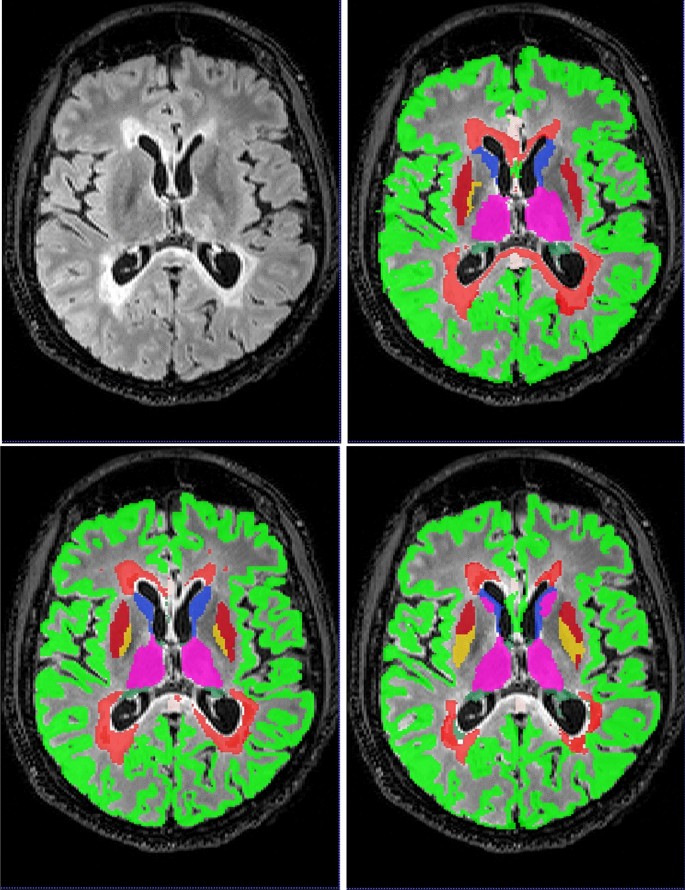

Box plots of the Dice coefficient for the segmentation (DeepSCAN multi-task) of various grey matter structures, when compared with Freesurfer, can be found in Fig. 3. Both models performed quite robustly when applied to the Insel32 dataset. However, the nnUnet model can be seen to make substantial errors in the placing of structures on the MSSEG (out of sample) dataset, as can be seen in Fig. 4.

Boxplots of Dice coefficients for selected grey matter structures, for classifiers trained on the Insel90 dataset, and validated on the Insel32 (in sample) and MSSEG (out of sample) datasets.

An axial slice of case 1016SACH from the MSSEG dataset. Top left, FLAIR, top right, fused ’ground truth’, bottom left, DeepSCAN segmentation, trained on the Insel90 dataset, bottom right, nnUnet segmentation, trained on the same Insel90 dataset. nnUnet model incorrectly labels parts of Caudate nucleus as Thalamus, and incorrectly places boundary between Pallidum and Putamen.